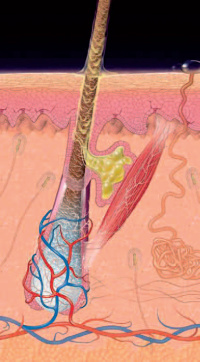

Gruczoły łojowe to bardzo ważne struktury budowy naszej skóry, biorące udział w wielu, zarówno biernych, jak i aktywnych jej funkcjach.

Gruczoły łojowe to bardzo ważne struktury budowy naszej skóry, biorące udział w wielu, zarówno biernych, jak i aktywnych jej funkcjach.

Skóra ludzka pełni wiele różnorodnych funkcji, zarówno biernych (np. ochrona przed ciepłem, zimnem, promieniowaniem, czuciem ucisku, dotyku, uderzenia, ochrona przed substancjami chemicznymi, ochrona mechaniczna przed wnikaniem drobnoustrojów), jak i czynnych (m.in. ochrona przed mikroorganizmami, wchłanianie substancji czynnych, wydalanie potu i chłodzenie, regulacja krążenia krwi i termoregulacja). Jest też narządem zmysłu odbierającym bodźce ucisku, drgania, ból i temperaturę. Ponadto bierze udział w procesach immunologicznych i współdecyduje o kształcie ciała. Fizjologiczne funkcjonowanie skóry jako bariery chroniącej organizm uwarunkowane jest prawidłową budową wszystkich jej warstw, odpowiednim stopniem nawilżenia oraz prawidłową strukturą płaszcza hydrolipidowego.

Skóra ludzka pełni wiele różnorodnych funkcji, zarówno biernych (np. ochrona przed ciepłem, zimnem, promieniowaniem, czuciem ucisku, dotyku, uderzenia, ochrona przed substancjami chemicznymi, ochrona mechaniczna przed wnikaniem drobnoustrojów), jak i czynnych (m.in. ochrona przed mikroorganizmami, wchłanianie substancji czynnych, wydalanie potu i chłodzenie, regulacja krążenia krwi i termoregulacja). Jest też narządem zmysłu odbierającym bodźce ucisku, drgania, ból i temperaturę. Ponadto bierze udział w procesach immunologicznych i współdecyduje o kształcie ciała. Fizjologiczne funkcjonowanie skóry jako bariery chroniącej organizm uwarunkowane jest prawidłową budową wszystkich jej warstw, odpowiednim stopniem nawilżenia oraz prawidłową strukturą płaszcza hydrolipidowego.